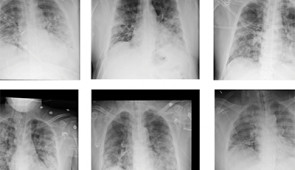

X-ray samples

Sample of most representative images from different classes of DeepCOVID-XR predictions relative to the reference standard. Credit: Northwestern University